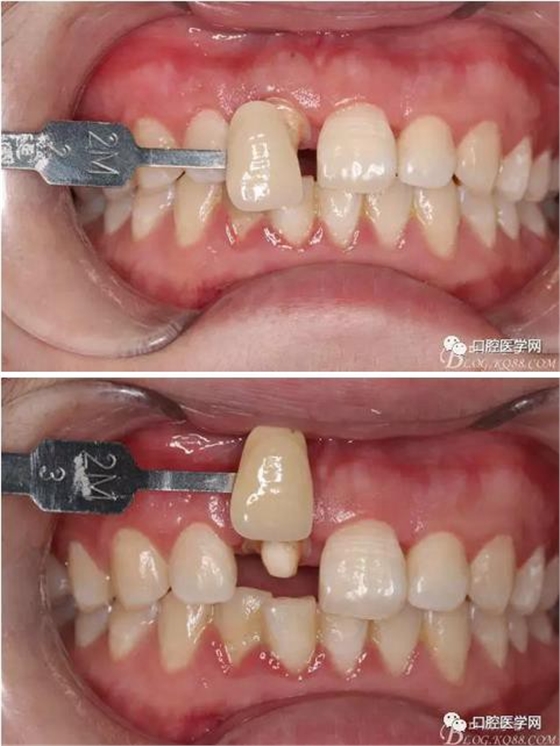

術(shù)前口內(nèi)照,11殘根,唇側(cè)牙齦紅腫,肩臺在齦下2毫米,舌側(cè)正常.21有被動萌出,長寬比例不協(xié)調(diào)??谇恍l(wèi)生一般,有菌斑。

術(shù)前原有牙冠復(fù)位,牙齦紅腫。

比色